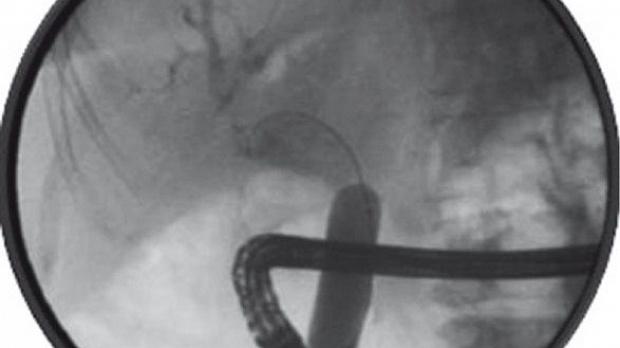

Интракорпоральная литотрипсия длилась 25 минут и позволила раздробить и извлечь фрагменты конкремента с помощью корзины Dormia и баллонного катетера (рис. 3).

Рисунок 3 [1].

В конце процедуры проходимость общего желчного протока и культи пузырного протока была восстановлена (рис. 4).

Рисунок 4 [1].